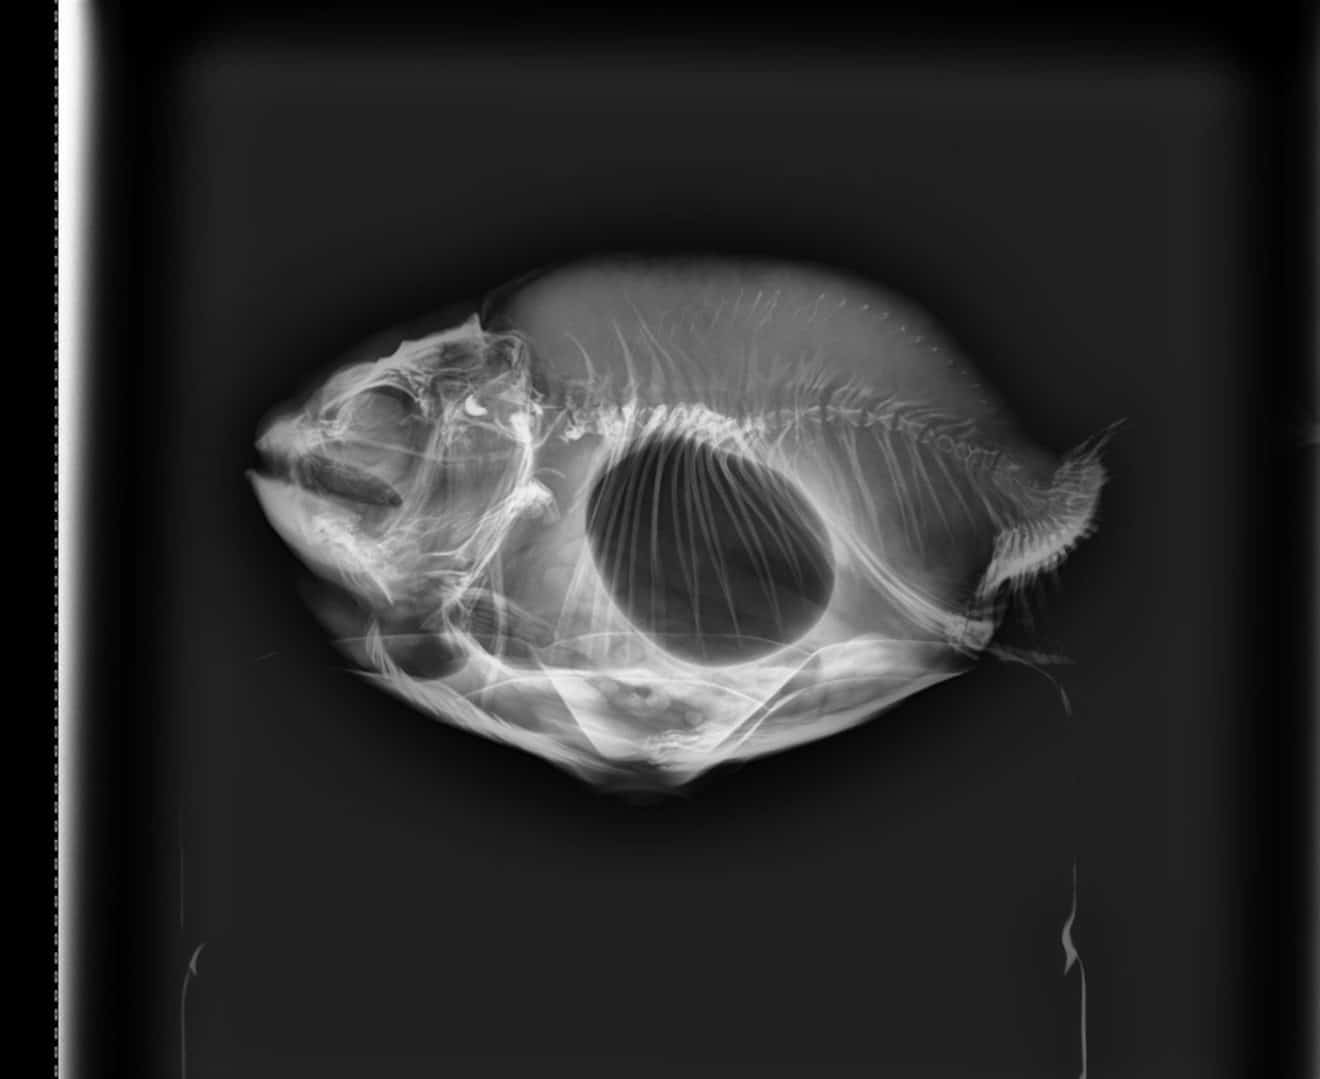

Buoyancy disorder WHWildgoose fish vet Positive Buoyancy Disorder the signs of swim bladder disease in goldfish are swimming in odd ways, swimming while upside down, or sitting at the bottom of the tank upside. from time to time, some fish may develop swim bladder problems and these tend to manifest as buoyancy. swim bladder disease is a syndrome that affects fish buoyancy and can be. Positive Buoyancy Disorder.

Leafy seadragon with positive buoyancy disorder due to swim bladder Positive Buoyancy Disorder the signs of swim bladder disease in goldfish are swimming in odd ways, swimming while upside down, or sitting at the bottom of the tank upside. positive buoyancy disorder, where the fish floats at the surface or on its side, is the most commonly presented. from time to time, some fish may develop swim bladder problems and. Positive Buoyancy Disorder.